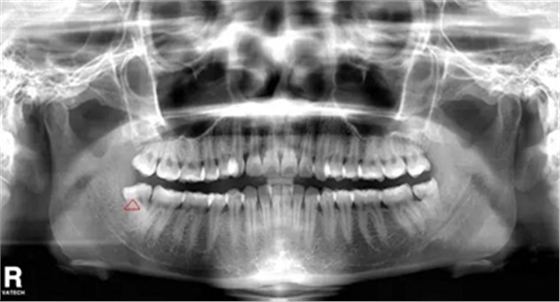

智齒遠中阻生(遠離鄰牙方向長)反復(fù)炎癥感染

5.反復(fù)發(fā)炎的智齒